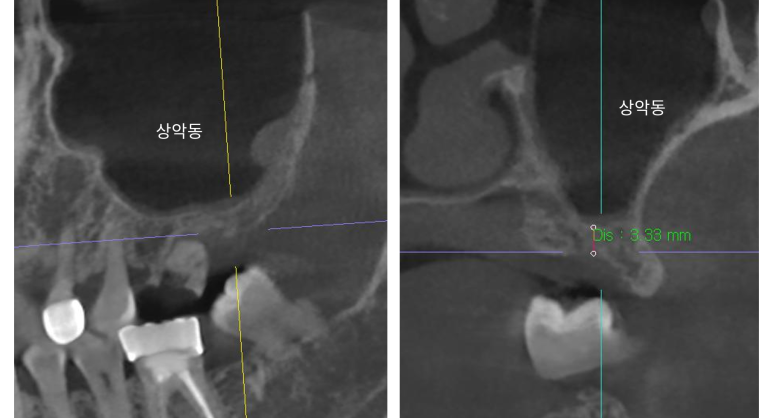

CT 촬영 결과,

해당 부위는 골 높이 3~5mm 수준으로,

단순 식립만으로는 충분한 고정력을 확보하기 어려웠습니다.

다행히도:

- 상악동 점막이 건강하고

- 바닥(저부) 형태가 평탄하여

잇몸을 크게 절개하지 않는 수압 거상술로 접근하였습니다.

🔍 오늘하루치과의 진단 기준

- 3D CT 정밀 촬영

- 상악동 모양, 점막 상태, 골 밀도 확인

- 비수술 접근 가능한 조건인지 평가

- 수압 거상술 또는 측방 접근 여부 결정